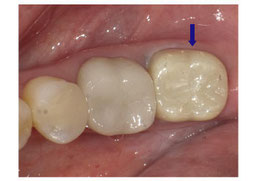

現在当院では臼歯部でセラミックの詰め物・かぶせ物をご希望の場合、ジルコニアを選択していただく患者様が増えております。

セラミックに比べると透明感がなく真珠のような質感をしています。ですので前歯などの審美的な部分に使用する場合は、セラミックを築盛します。

しかし、透明感がないことにより土台の色が合わない場合、透けてこないという利点もあります。